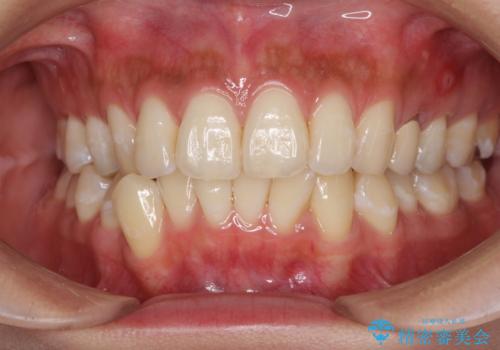

八重歯の再矯正 インビザラインでストレスなく矯正治療

- 学生の頃に矯正治療を行ったものの、保定を怠けてしまったことによる後戻りを気にして来院された患者様です。

根管治療が必要な歯があったため、矯正治療前に根管治療を行い、その後はインビザラインにより矯正治療を行うこととしました。

矯正治療後には根管治療を行った歯の補綴治療を行うこととしました。

下顎の八重歯が上顎歯列に収まる過程で咬みにくさがありましたが、最終的には、咬み合わせも安定し、きれいに歯列を整えることができました。